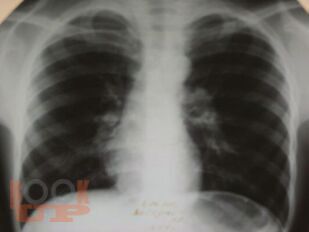

В учебно-методическом пособии отражена характеристика такого инфекционного заболевания как туберкулез, которое по-прежнему остается серьезной проблемой во всем мире. Дана характеристика основных групп риска развития туберкулеза, так как в группах риска заболеваемость туберкулезом в несколько раз выше, чем среди остальной части населения Российской Федерации и Ставропольского края. В пособии дано определение состоянию латентной туберкулезной инфекции, и подробно изложены методы ее диагностики. Также отражены основные направления профилактических мероприятий среди всех возрастных категорий, позволяющие снизить напряженность эпидемической ситуации по распространению туберкулеза.